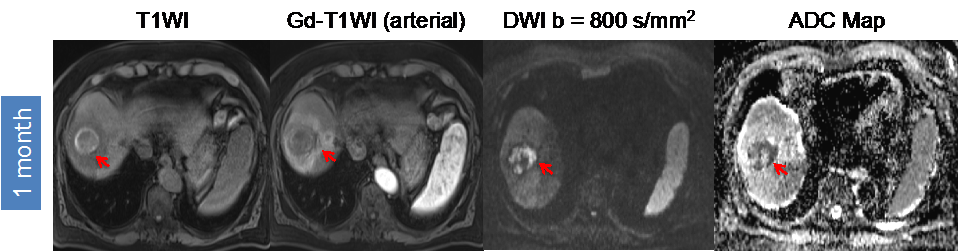

Figure 4.

Hemorrhage causes “pseudo-restriction” on DWI. 62-year-old man with segment VIII HCC (arrow) without macrovascular invasion or extra-hepatic disease who underwent radioembolization segmentectomy therapy. There is no Gd-enhancement on one month post-procedural MRI. However, there is significant hyperintensity on pre-contrast images. Although the absence of enhancement correlates with absent diffusion restriction, the presence of hemorrhage creates “pseudo-restriction” without the presence of viable tumor. This pitfall has to be recognized.

Furthermore, more technically-oriented challenges, biologic properties and alterations of the tumor can affect the diffusion estimate of the ADC method. As an example, post-treatment hemorrhage of the tumor may mask the treatment related ADC value increase caused by tumor necrosis, but can be detected with conventional MRI as illustrated in Figure 4 [39,40]. Depending on the settings, the ADC values can be substantially “contaminated” by capillary microperfusion when lower b-values and a mono-exponential model, which does not represent “pure diffusion”, are used. The microperfusion fraction can be reduced but not eliminated by using higher b-values ≥50 s/mm2 for the ADC calculation. Since the perfusion fraction of the HCC lesions cannot be predicted and may vary between tumors and different time points, it can represent a source for variations of measured ADC values [52,60].